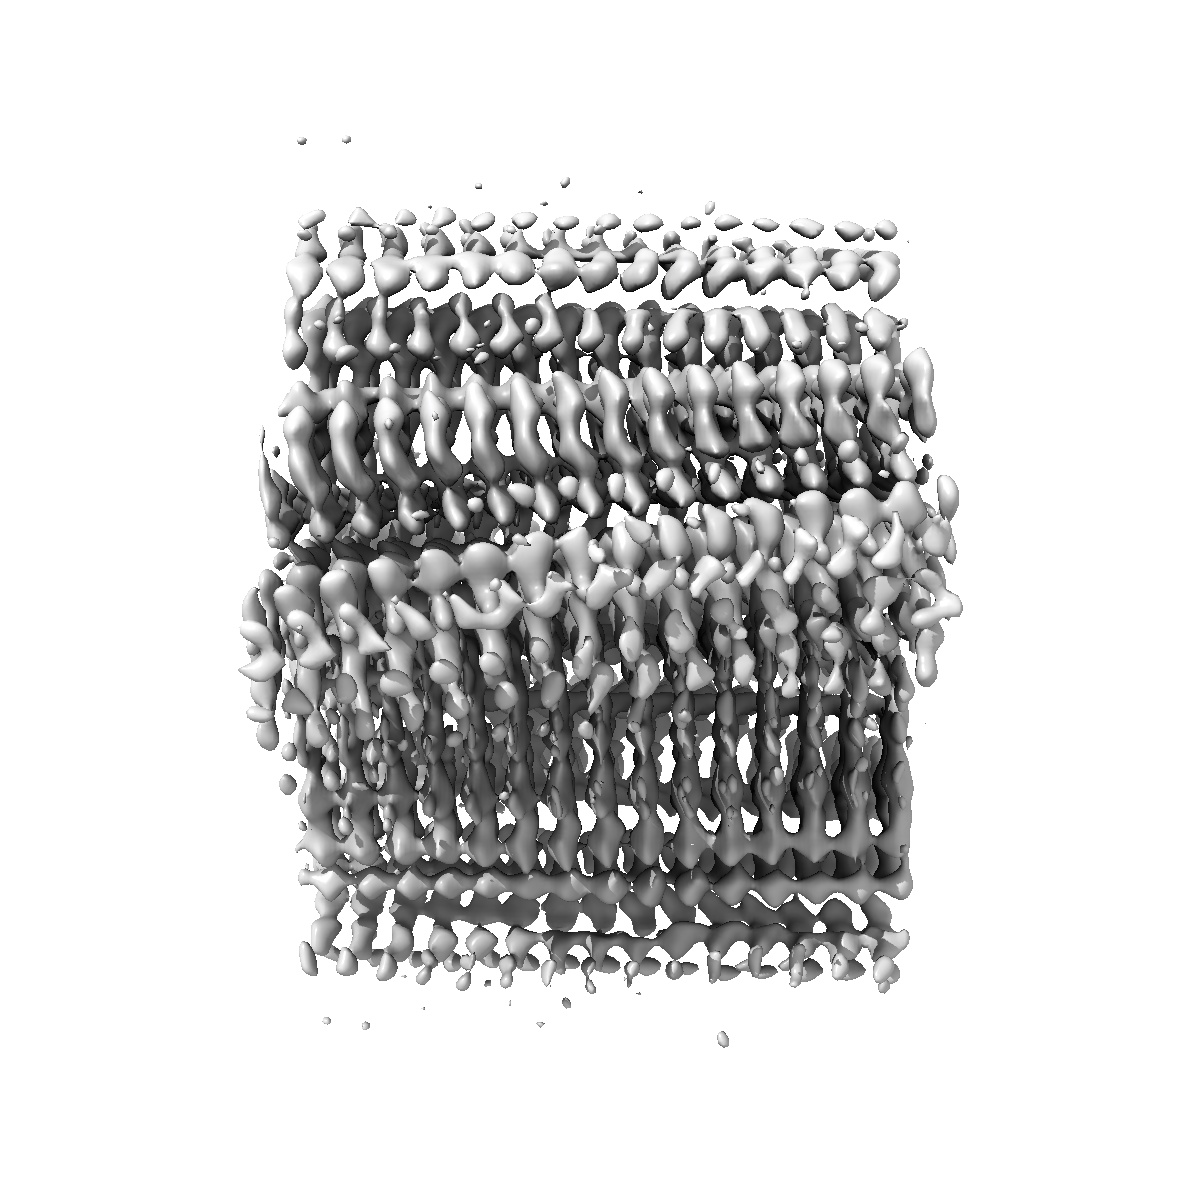

Structure of amplified aSyn filament by using seed amplification assay (SAA) from MSA patient CSF.

Helical reconstruction3.9 Å

Sample: Alpha-synuclein protein filament

Seed amplification of MSA alpha-synuclein aggregates preserves the biological and structural properties of brain-derived aggregates.